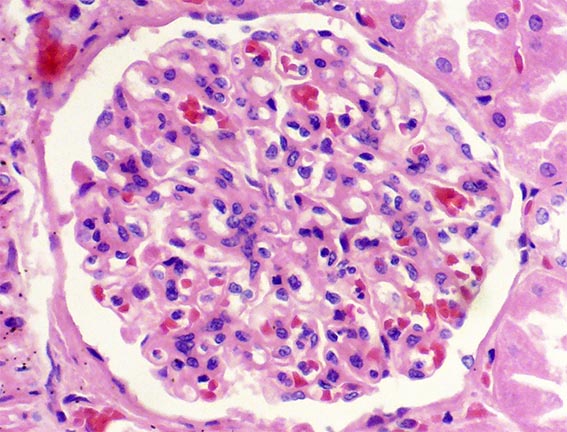

Figura 1. H&E, X100.